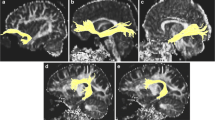

The reconstruction of the tracts of interest was possible using the deterministic method FACT and ROIs obtained for each subject by the transformation proceeding of reconstruction of the trajectory proposed for ten tracts of interest in each of the 84 subjects enrolled in the study. These tracts were classified for description in four functional categories: brainstem fibers and projection, association fibers, tracts of the limbic system and commissural fibers (See Additional file 1).

Volume

The GLM Repeated Measure ANOVA using Tracts volume as repeated measures, Gender as categorical predictor and Age as continuous predictor showed that exist a main effect of Tracts volume (F = 26.40, df = 17, p < 0.001, ɛ = 0.425) and Gender (F = 11.98, df = 1, p = 0.001) (Fig. 1). The double interaction Tracts x Gender was significant (F = 5.929, df = 17, p < 0.001, ɛ = 0.425). The planned comparison analysis showed that the volume in female are significant larger than males for left ATR (F(1,81) = 22.366; p < 0.001), right ATR (F(1,81) = 7.958; p = 0.006), right CGH (F(1,81) = 5.609; p = 0.020), Fmj (F(1,81) = 21.654; p < 0.001) and Fmn (F(1,81) = 12.896; p < 0.001). The remaining tracts had larger volumes in females than males with no significant differences, with the exception of right CST and right UNC which presented larger volume for males (Fig. 1).

Excluding the commissural tracts, Fmj and Fmn, hemispheric asymmetries in volume were assessed by GLM Repeated Measure ANOVA using Tracts volume and Hemisphere as repeated measures, Gender as categorical predictor and Age as continuous predictor, showed that exist a main effect of Tracts (F = 19.69, df = 7, p < 0.001, ɛ = 0.618) and Hemisphere (F = 11.9, df = 1, p < 0.001). The double interaction Tracts x Hemisphere (F = 2.041, df = 7, p < 0.05) were significant. Planned comparison showed that the volume in the left hemisphere is larger than the right in both genders for the following tracts: ATR (F(1,81) = 52.461; p < 0.001), CGC (F(1,81) = 15.28; p < 0.001), CST (F(1,81) = 4.608; p = 0.035), ILF (F(1,81) = 18.968; p < 0,001) and SLF (F(1,81) = 34.558; p < 0.001).On the contrary, the volume in the right hemisphere was larger in CGH (F(1,81) = 5.624, p = 0.02) and the IFOF (F(1,81) = 12.377; p < 0,001). No significant differences between hemispheres in the volume of UNC were founded.